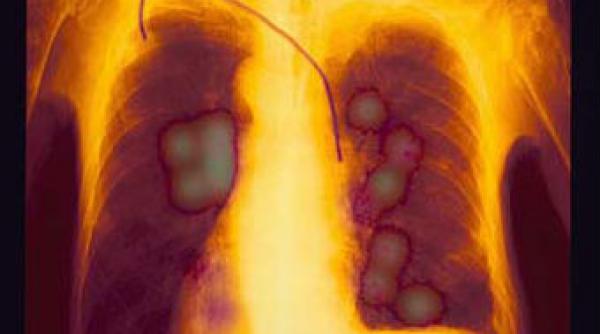

Cancerul, scos la iveală prea târziu. La 70% dintre pacienţii cu cancer pulmonar şi 60% cu cancer renal boala este descoperită în ultimele stadii

Un tratament experimental permite prelungirea vieţii în cazul bolnavilor de cancer pulmonar în fază avansată